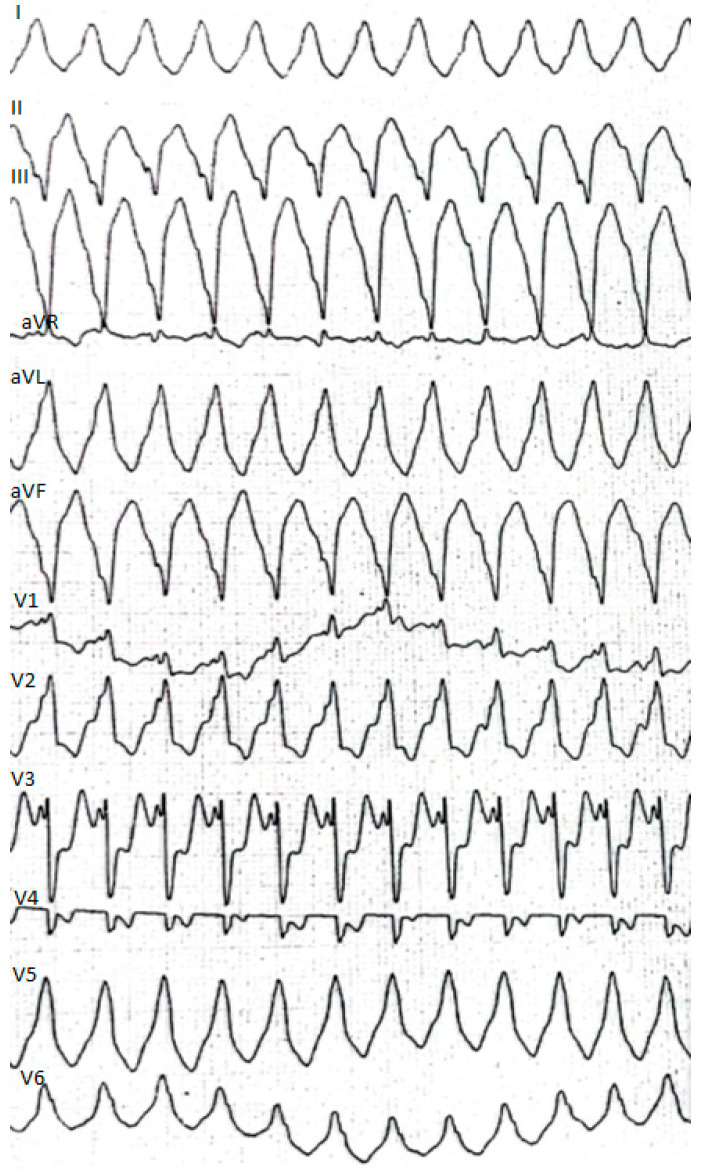

This time the individual was admitted to our cardiology center after another episode of VT, with cardiac arrest in the mechanism of VT at an emergency room (VT score—4 points, positive result of the Vereckei, Brugada and limb algorithms for the diagnosis of VT on ECG, Figure 4) treated with electrical cardioversion for further treatment [ref. 9,ref. 10]. The physical examination showed no significant abnormalities, the patient’s weight was 69 kg, height—190 cm, body mass index–BMI–19.11 kg/m2. Peripheral blood saturation—96%, body temperature—36.7 degrees C. Blood pressure was in the range of 100–110/60–70 mm Hg. In laboratory tests: white blood cells count—WBC—8.45 K/µL; hemoglobin—Hgb—13.3 g/dL; platelets count—PLT—260 K/µL; troponin T—317.6 ng/mL (norm < 30); N-terminal pro-brain natriuretic peptide—NT-proBNP—905 pg/mL; creatine phosphokinase—CPK—352 U/L; MB iso-enzyme of creatine kinase-CK-MB-24 U/L (6.8% CPK); thyroid-stimulating hormone—TSH—0.805 µU/mL; total cholesterol—2.6 mmol/L; low-density lipoprotein cholesterol—LDL—1.35 mmol/L; high-density lipoprotein cholesterol—HDL—0.89 mmol/L; triglycerydes—TG—0.87 mmol/L; glucose—5.6 mmol/L; creatinine—77 µmol/L (estimated glomerular filtration rate—eGFR > 90 mL/1.73 m2/min); sodium—141 mmol/L; potassium—3.61 mmol/L; chlorides—102 mmol/L; C-reactive protein—CRP—1.0 mg/L; d-dimer—413 ng/mL; alcohol—0.2 per mille; international normalized ratio- INR—1.23; activated partial thromboplastin time—aPTT—34 s; Abbott antigen test for SARS-CoV-2 virus negative; PCR test for COVID-19 also negative. The resting electrocardiogram revealed a sinus rhythm of 76 beats/min, the axis of the heart inclined moderately to the right, low voltage of QRS complexes in the limb leads, negative T waves in V5 and V6, and positive–negative in aVL. PQ equaled 160 ms, QRS—90 ms, QTc—440 ms (Figure 1, right panel). On echocardiography, the left ventricle was not enlarged (its end-diastolic dimension—55 mm), the interventricular septum was moderately thickened (11 mm in the diastolic phase), normal left ventricular systolic function was observed, with no segmental abnormalities of contractility (left ventricular ejection fraction—LVEF was 55%). No other significant abnormalities, including significant valve defects, were observed.